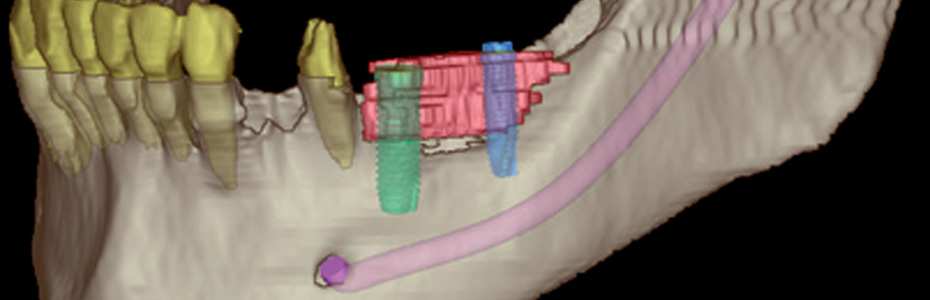

Die perfekte Position des Implantats ist entscheidend für den dauerhaften Behandlungserfolg. Nicht nur die ausreichende Knochensubstanz ist hierfür wichtig. Bei der Positionierung des Implantats gilt es darauf zu achten, dass keine Wurzeln oder Nerven verletzt werden. Zudem müssen Tiefe und Ausrichtung des Implantats genau stimmen, damit später der Zahnersatz – die Krone, Brücke oder Prothese – exakt angepasst werden kann.

Auf herkömmlichen Röntgenbildern sind oftmals wichtige Informationen nicht erkennbar. Abhilfe schafft hier die computergestützte, dreidimensionale Implantatplanung. Der nötige Abstand zu sensiblen Nerven und die optimale Implantattiefe werden bei der computergestützten 3-D-Planung exakt berechnet. Eine Software ermöglicht eine dreidimensionale Planung am Bildschirm und bietet beste Voraussetzungen, um das Implantat sicherer und genauer setzen zu können. Dies erfolgt über Schablonen die auf Grundlage einer individuellen 3D-Planung Hergestellt werden.

Durch die 3D-Planung kann außerdem die Ästhetik bereits vor dem Einsetzen der Implantate exakt vorausgeplant werden.